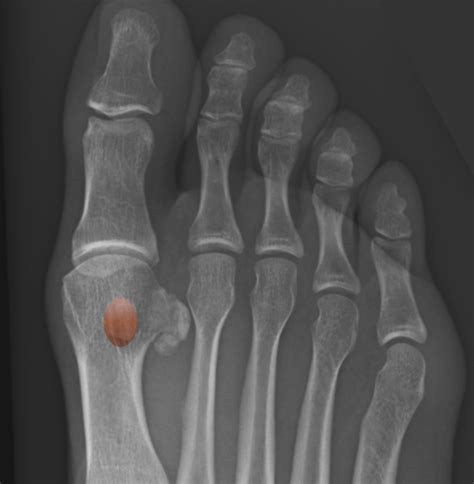

The sesamoid bones are two small, pea-shaped bones embedded within the tendons of the foot. They are located beneath the big toe and act as pulleys, helping to increase the mechanical advantage of the tendons. This allows for smoother and more efficient movement of the foot. The sesamoid bones also help to distribute weight evenly across the foot, reducing pressure on the ball of the foot.

• X-Rays: X-ray images to visualize the bones and identify any fractures.

• MRI or CT Scan: Advanced imaging techniques to provide a more detailed view of the sesamoid bones and surrounding tissues.